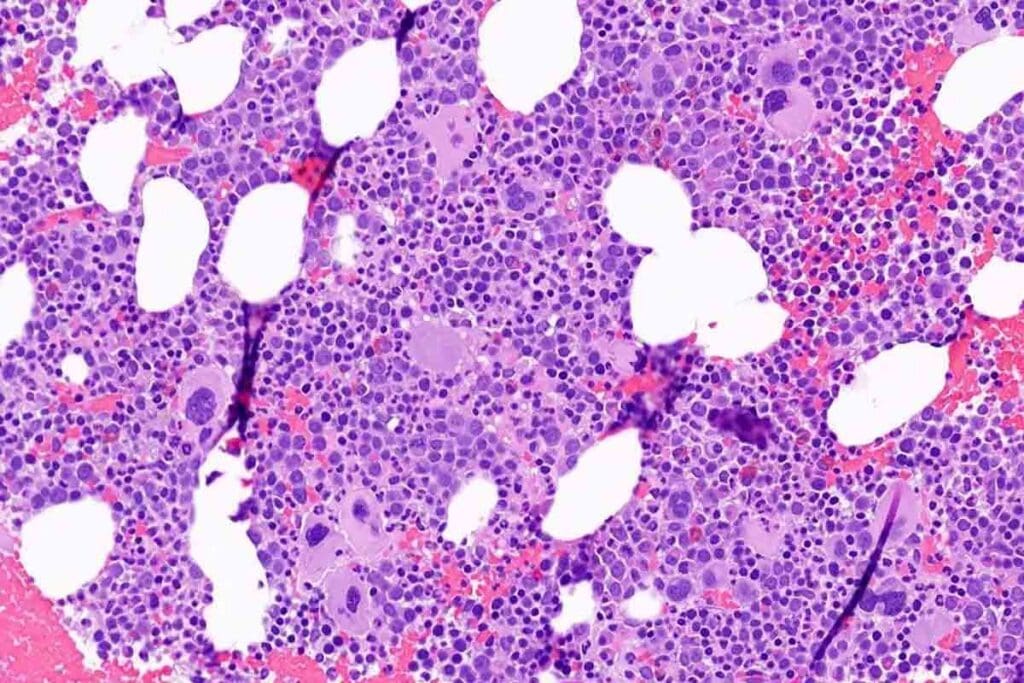

Bone Marrow Histology in Aplastic Anemia

Bone marrow biopsy is key to diagnosing aplastic anemia. The findings typically show:

- A hypocellular marrow, with a big drop in hematopoietic cells.

- An increase in fat cells changes the marrow’s look.

- Absence or reduction of megakaryocytes, myeloid, and erythroid precursors.

These signs are important for telling aplastic anemia apart from other pancytopenia causes.

Bone Marrow Cellularity and Long-term Outcomes

Bone marrow cellularity is also a key factor. Aplastic anemia is marked by a hypocellular bone marrow, filled with fat cells. How hypocellular it is shows how severe the disease is.

Those with very hypocellular marrow face a tougher prognosis than those with moderate hypocellularity. Recovery of bone marrow function, either on its own or with treatment, affects long-term outcomes.